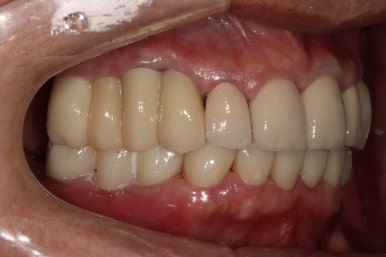

그렇게 완성된 최종 보철물 형태입니다.

임시치아와 다르게 지르코니아 크라운으로 제작되어 훨씬 단단하고 매끈하고 이상적인 형태를 가진걸 보실 수 있으실거에요.

위 아래 앞니 모두 적절한 길이로 회복이 되었고, 어금니도 이상적인 형태를 보여주고 있습니다.

좌우로 옆에서 봤을 때도 충분히 기능이 잘 되게끔 잘 물리는 어금니를 보실 수 있을거에요.

식사 시 음식이 덜 끼도록 치아와 치아사이를 최대한 닫아놓은 모양입니다.

위아래 모두 아주 이상적인 형태로 제작된 치아모양의 지르코니아 크라운을 보실 수 있을거에요.

이 정도면 전체 구강 재건 (full arch rehabilitation)이라고 불러야 합니다.